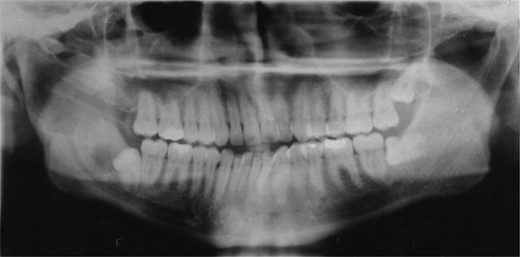

Radiographic examination over the following few months showed new bone formation and within 9 months of the initial biopsy the drain was expelled by formation of new bone (Fig. 3). One year after the commencement of treatment the patient was admitted for enucleation of the cystic remnant. At the time of this procedure a small cyst was removed from the right upper ramus and condylar neck, together, with a separate cyst associated with the lower right wisdom tooth. The patient made an uneventful post-operative recovery and histology revealed two KCOTs with a thick parakeratinized type of epithelium typical of radicular cysts.